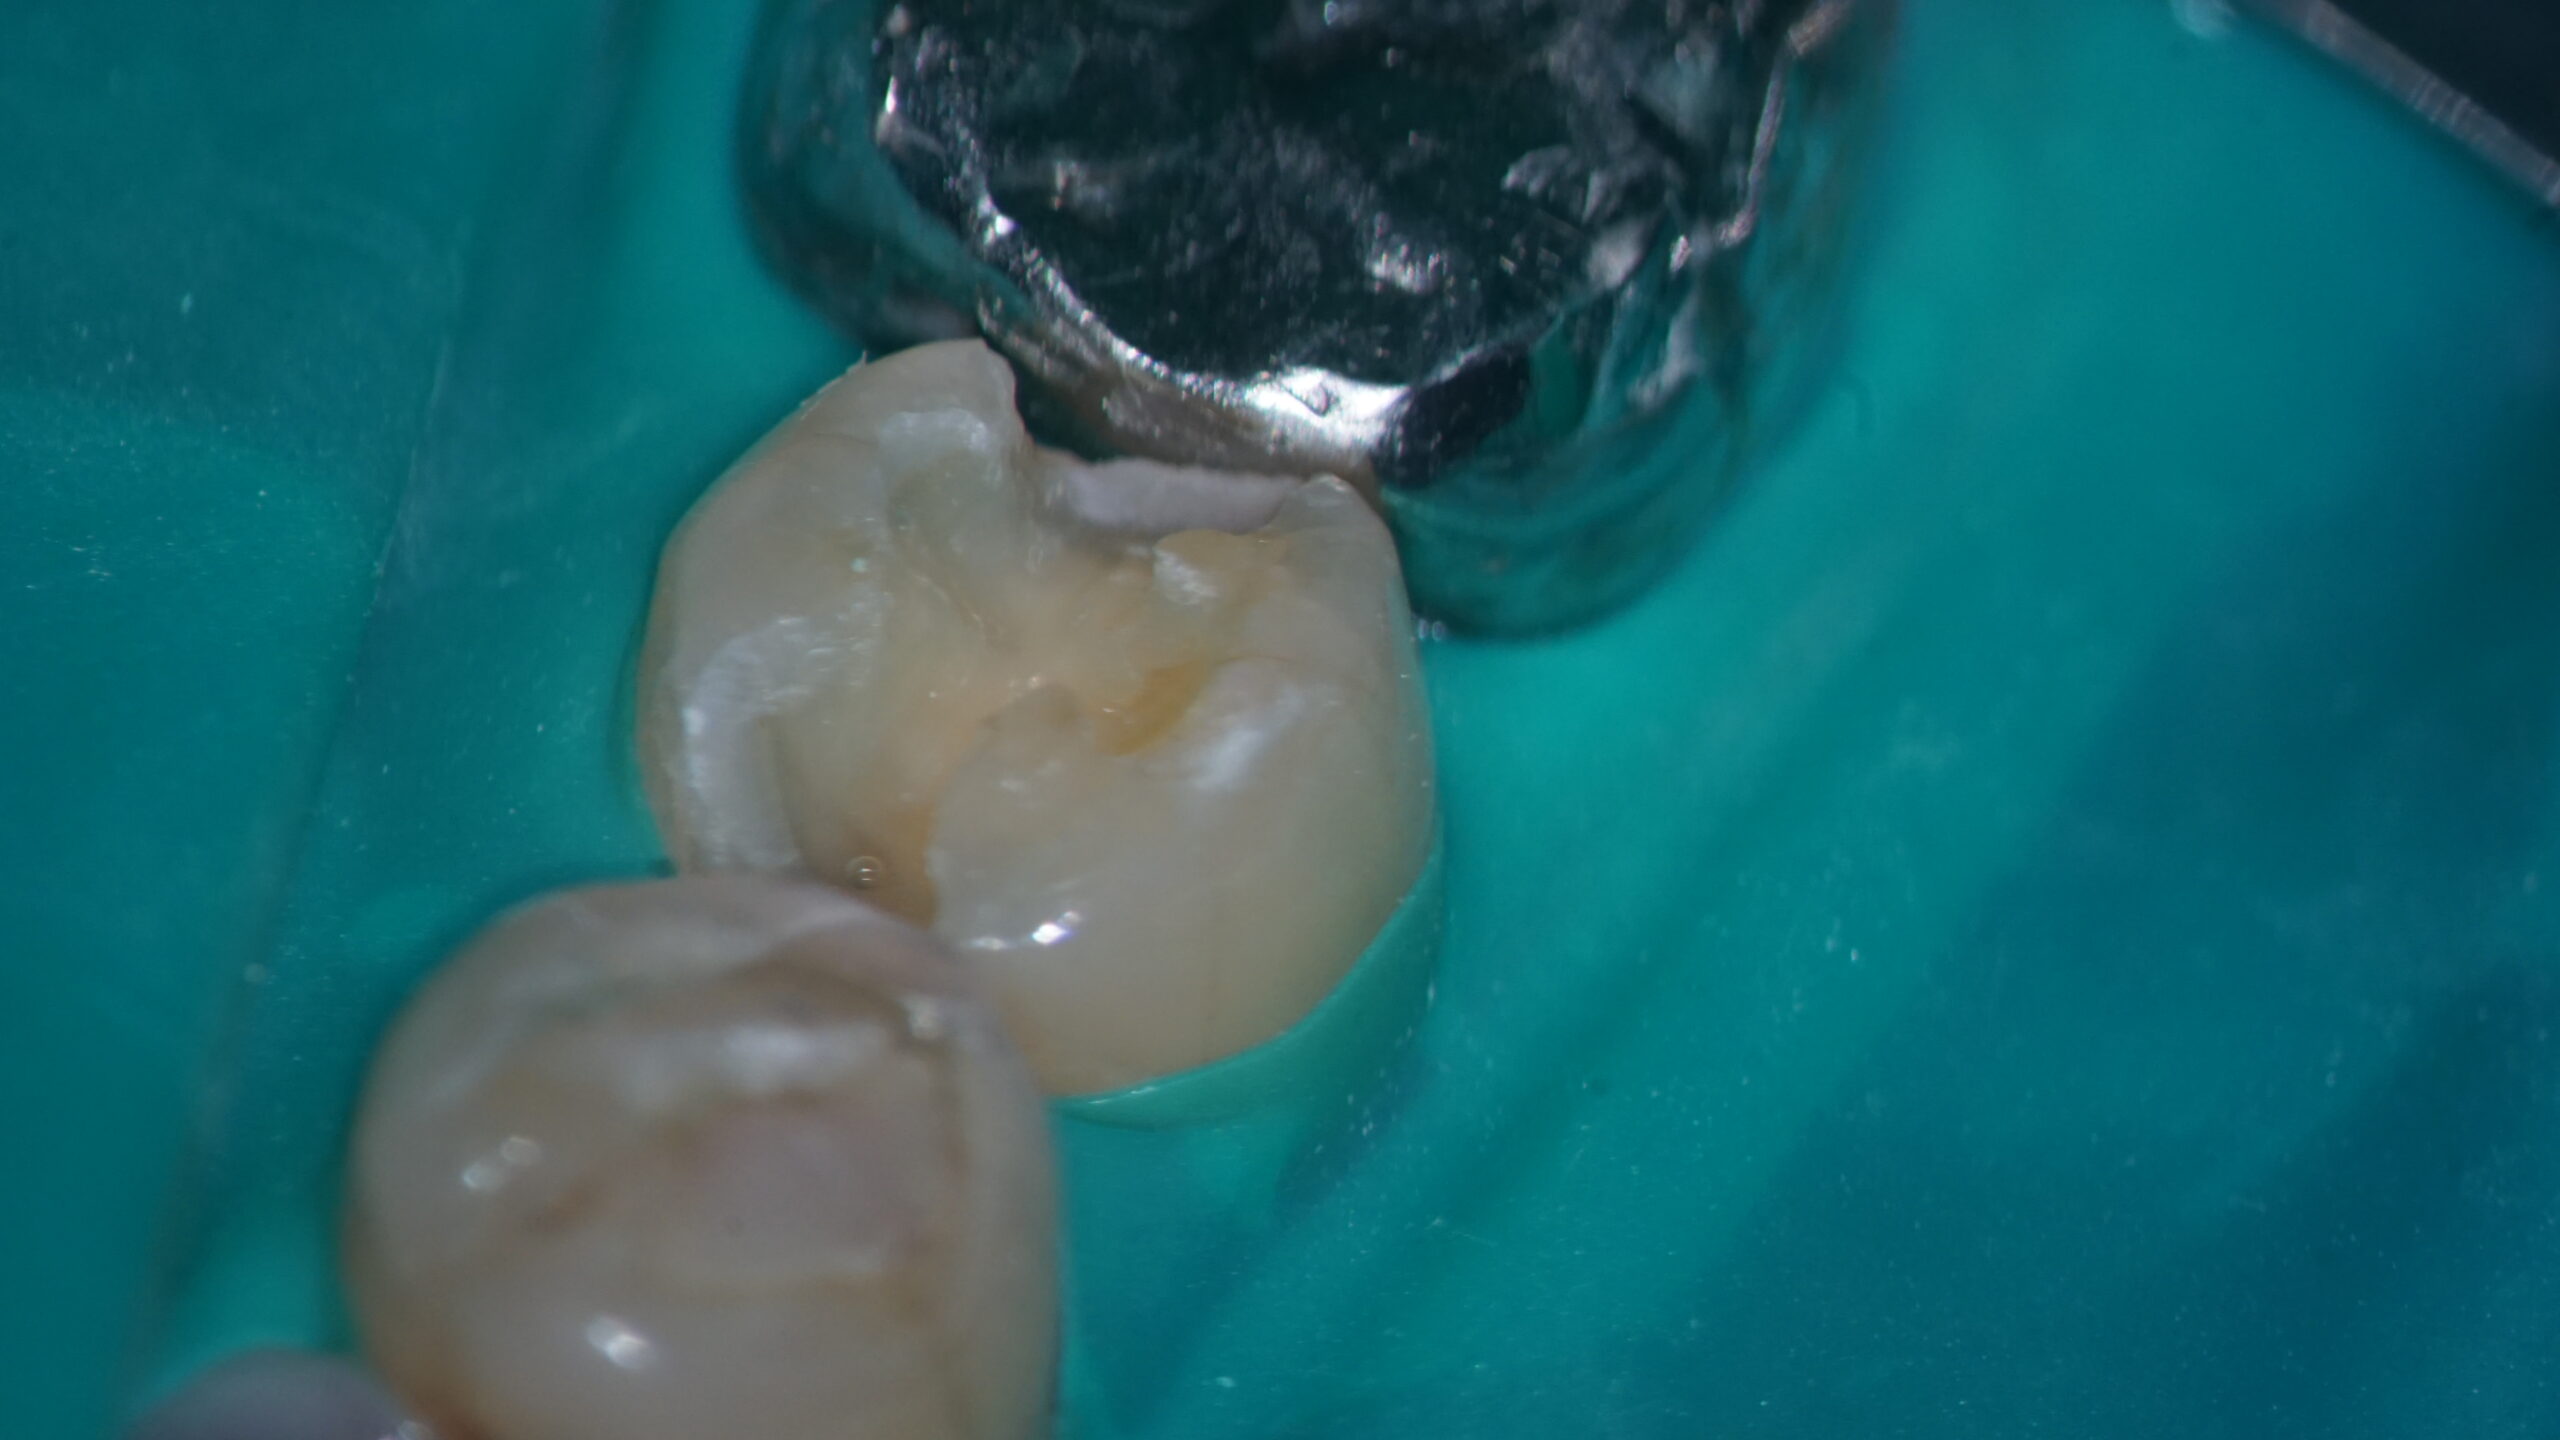

そのためには、歯の神経を保存する治療が欠かせません。

重い虫歯になってしまったとしても、即座に神経を抜く治療だけが選択肢ではありません。

少しでも長く神経を保存できるように、私たちは、さまざまな方法について学んでまいりました。

治療の前には、マイクロスコープを使用してお口の検査を行います。

そして、肉眼では捉えられない細部までしっかりと見極めて治療をすることは、トラブルの再発防止にもつながります。

一本でも多くの歯を守っていくためには、精密な検査や治療が欠かせません。

そのためにMTA治療をはじめ、神経を維持していくための治療について研鑽を積んできました。